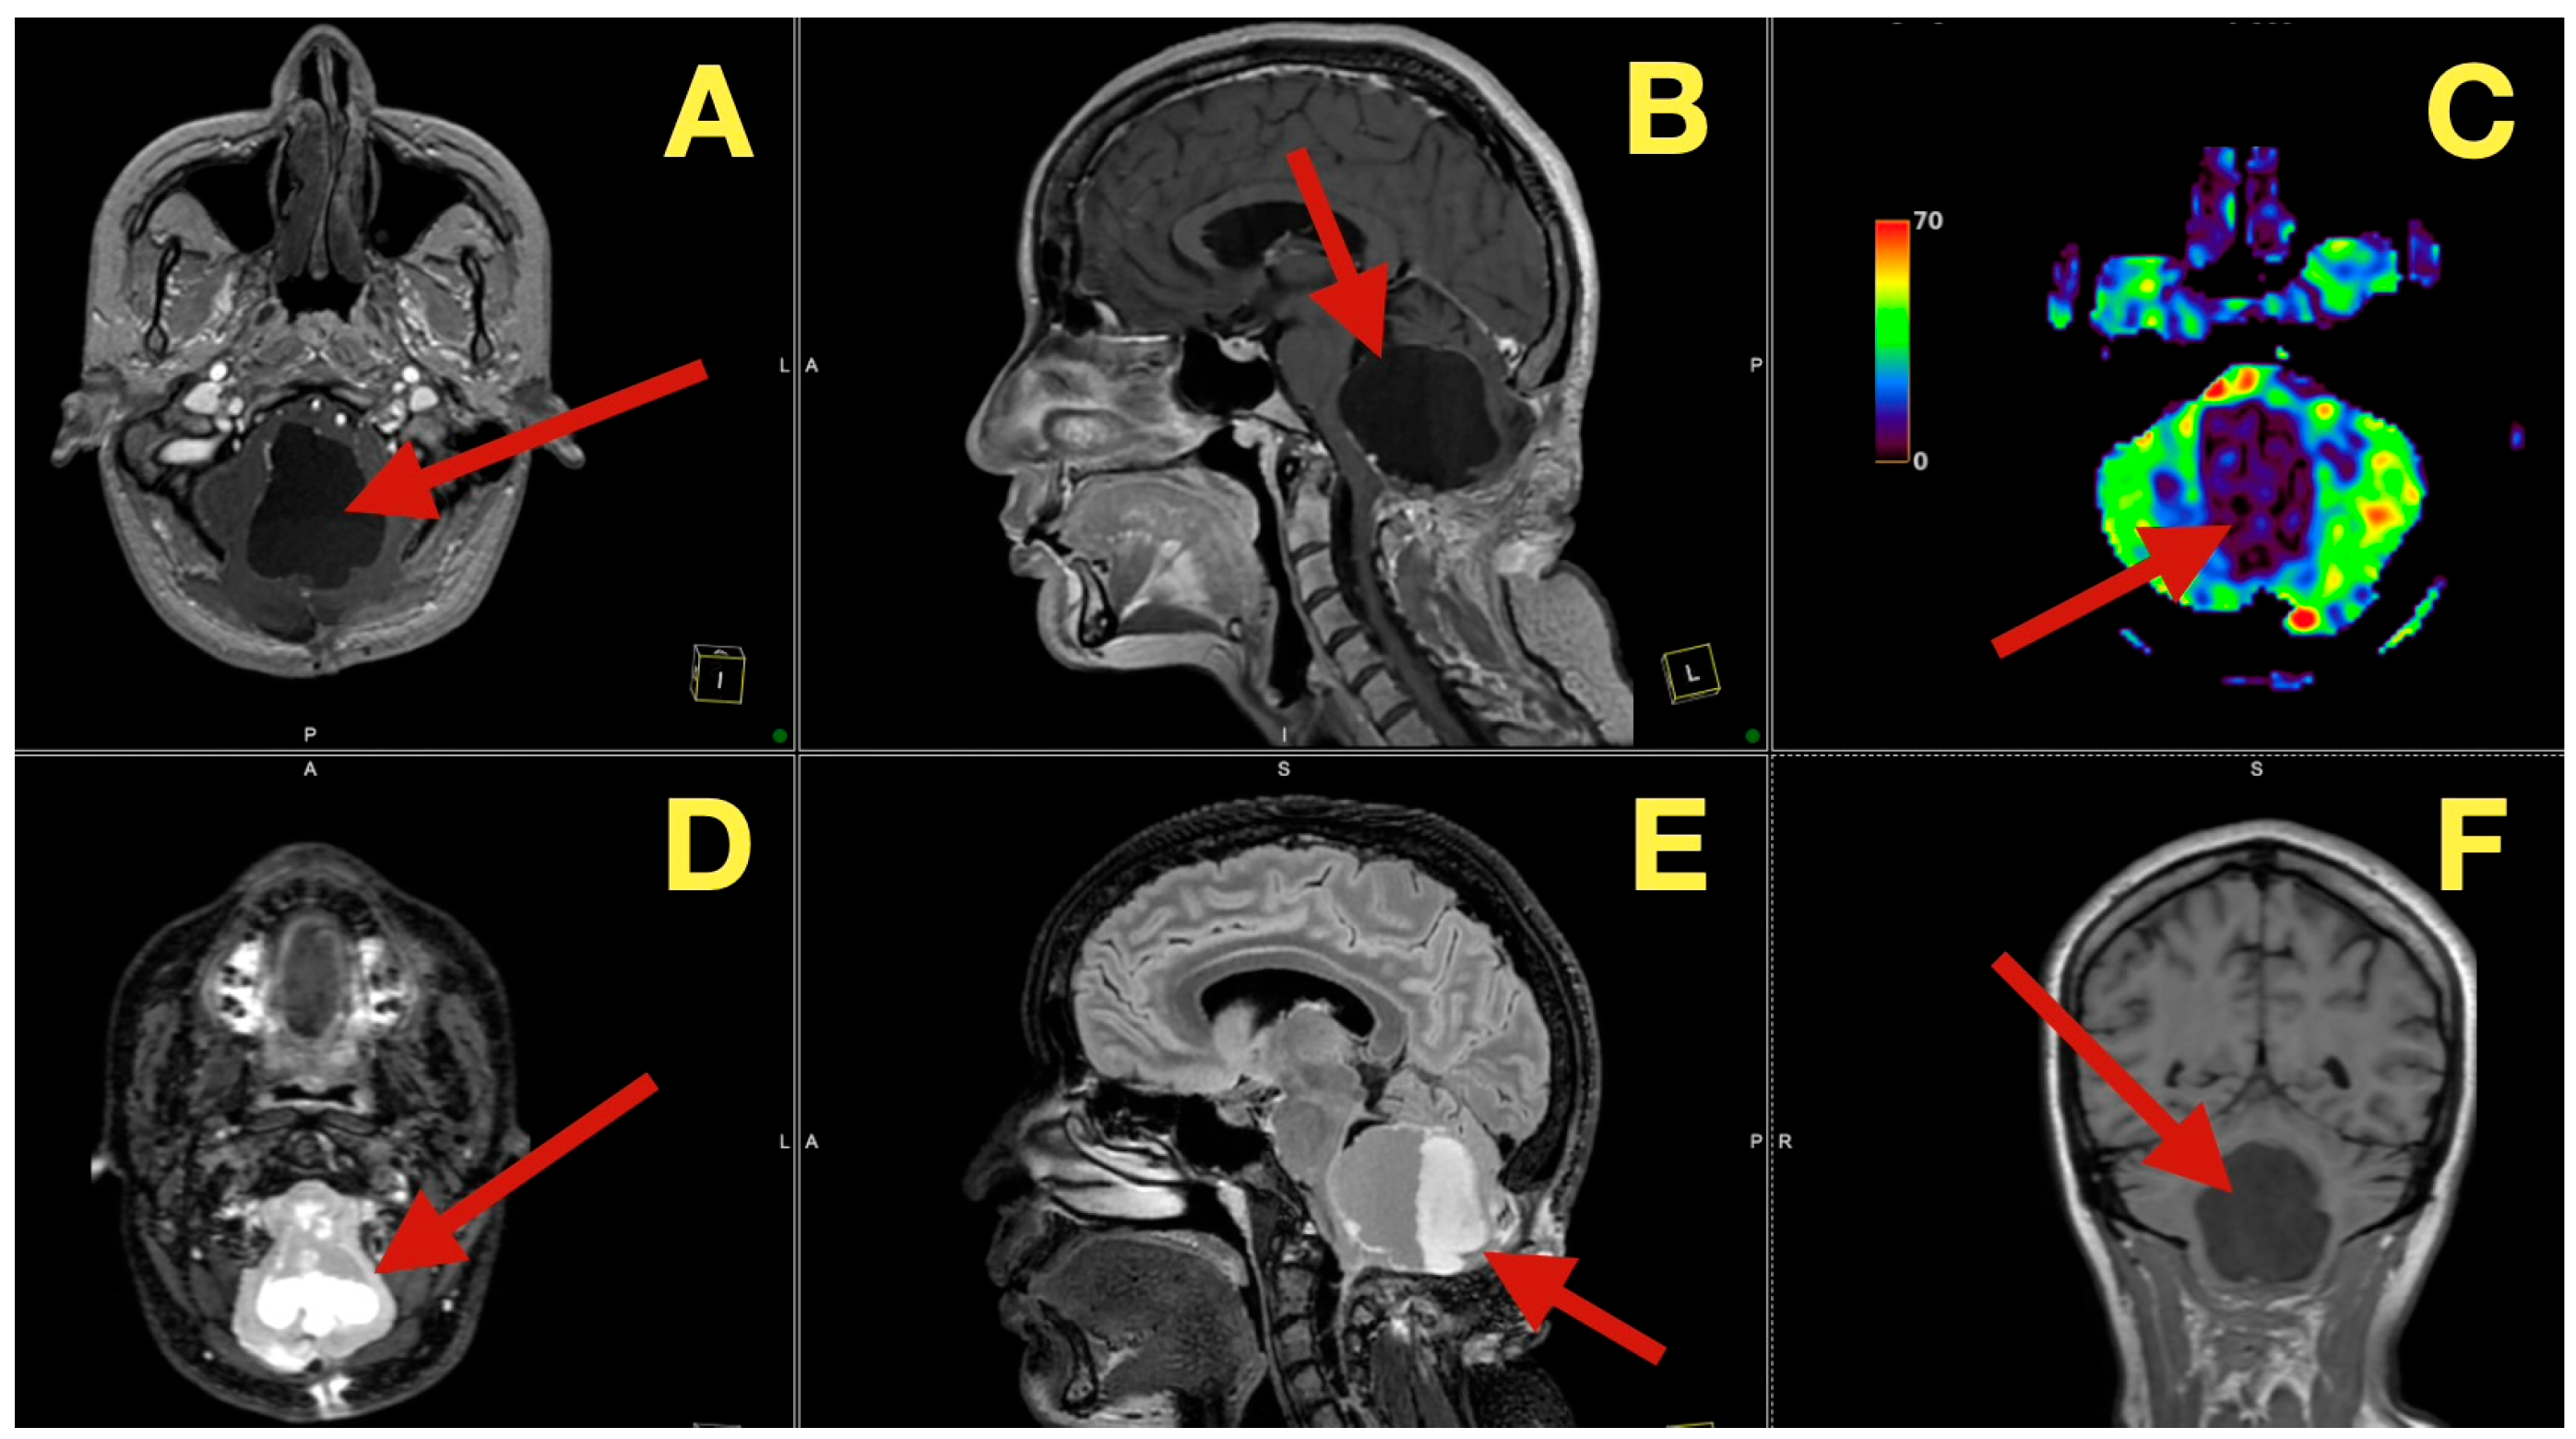

The preoperative MRI demonstrated a multilobulated mass within the fourth ventricle which was molded to the roof and cavity of the fourth ventricle. The mass arose from the inferior portion of the vermis and draped over the superior medullary velum and had smooth interfaces with the surrounding parenchyma which it displaced but did not invade. The mass was uniformly hypointense on T1 images; however, on T2/FLAIR images, the mass had hyperintensity with internal lobulation. The mass marginally compressed the uvula and nodulus and compressed the posterior surface of the pontine-medullary tegmentum. The foramen of Magendie was obliterated and both foramina of Luschka were narrowed resulting in an upstream flow void in the ventricles and a rim of periventricular interstitial edema. This created the hydrodynamic environment responsible for the patient’s symptoms. The worsening headache and vomiting in the morning, the papilledema, and nuchal rigidity resulted from the hydrodynamic environment. The avascular nature of the mass and the CSF conforming surface of the mass, as well as its central location, strongly suggested the possibility of an epidermoid cyst vs. a vascular neoplasm. The image-symptom correlation was excellent: the axial ataxia and titubation were due to compression of the fastigial nucleus and the vermian midline; the gaze-evoked nystagmus was due to disruption of the flocculonodular circuitry along the fourth ventricular roof; and the intracranial hypertension was due to obstruction of the caudal apertures. The morphology and epicenter of the mass were most consistent with a posterior fossa midline epidermoid tumor of Type 2 (fourth-ventricle epicenter) with a dominant relationship to the tela choroidea and cerebellomedullary fissure, anticipating a roof-centered growth pattern and possible focal adherence to the ventricular floor.

On the axial post contrast T1 plane (Figure 1A), the mass occupied the ventricular space like a mold, did not enhance, and was in the midline. The medial surface of the mass was in contact with the cerebellar vermis and the lateral surface of the mass slightly indented the tonsillar surfaces without penetrating into the parenchyma. On the mid sagittal T1 view (Figure 1B), the mass was in contact with the inferior vermis and caused an upward bowing of the superior medullary velum and flattening of the dorsal medulla and this explained the patient’s episodes of pressure-induced vomiting by mechanical stimulation of the area postrema. The coronal T1 reconstruction (Figure 1C) clearly demonstrated that the mass was in the midline and caused an equal compression of the two outlet recesses and was consistent with the absence of laterality in the patient’s deficits. On T2 (Figure 1D) and mid sagittal FLAIR (Figure 1E), the mass’ fluid-like appearance and internal lobulation were prominent; the surface of the mass was molded to the fourth ventricular CSF and not invading the fourth ventricular CSF, and this was a classic finding for this type of mass and accounted for the unusual severity of the fastigial/vermian hub being compressed and not destroyed.

Figure 1. Preoperative MRI of the posterior fossa. (A): Axial post-contrast T1: non-enhancing, lobulated mass centered in the fourth ventricle (arrow). (B): Mid-sagittal T1: inferior-vermis contact with upward bowing of the superior medullary velum and dorsal brainstem compression (arrow). (C): Coronal T1: strict midline localization with symmetric crowding of the ventricular outlets (arrow). (D): Axial T2: intrinsically high signal with molded margins against cerebellar tonsils (arrow). (E): Mid-sagittal FLAIR: high signal lesion with effacement of Magendie and narrowing of Luschka, concordant with obstructive hydrocephalus (arrow). Radioclinical correlation: vermian compression → truncal ataxia/titubation; flocculonodular disturbance → gaze-evoked nystagmus; outlet occlusion → intracranial hypertension.